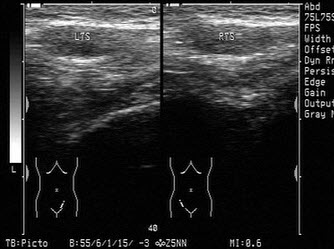

14、单项选择题

男,11岁,右侧阴囊空虚,左侧睾丸可触及,右侧腹股沟区可探及低回声肿块,如图所示,考虑为()

A.隐睾

B.淋巴结

C.腹股沟疝

D.腹股沟肿瘤

E.以上都不是